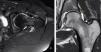

El pinzamiento femoroacetabular es una entidad patológica que se presenta en las consultas del aparato locomotor y que cursa con dolor e impotencia funcional de la cadera en el adulto joven. Se produce por un conflicto de espacio entre el componente femoral y el anillo acetabular en determinadas posiciones de la cadera. El origen puede estar en un defecto en la unión cabeza-cuello femoral, en un exceso de cobertura de la parte anterolateral del acetábulo o en ambas. Se desencadena un atrapamiento entre la unión cabeza-cuello y el reborde acetabular, que conducirá a una lesión inicial en la unión condrolabral y cuya evolución, si no se corrige, produce una degeneración precoz de la articulación.

Femoroacetabular impingement is a new pathological entity that is becoming more frecuently recognized in consults related to locomotor system. It appears when, due to a malformation in the femoral neck-head junction, a relative excess of bone in the anterolateral part of the acetabullum or both conditions together, a impingement is developed during the arc of movement of the joint, resulting in an initial chondrolabral lesion, being source of symptoms and functional impairment in the young patient. In case of no correction it will probably leads to secondary osteoarthritis when the cartilage lesion progress.